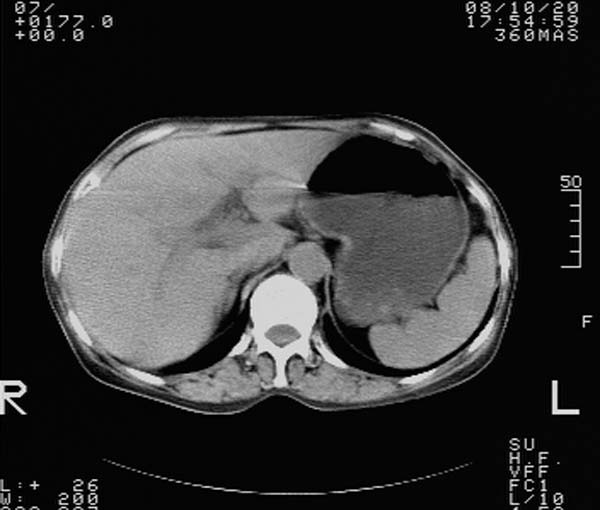

f,67y。反复右上腹痛。余无异常。

前五幅未服造影剂。后面图像有上传重复的。请战友们发表意见。

胆囊结石、胆囊癌伴邻近脏器受侵,不除外黄色肉芽肿性胆囊炎,建议增强扫描。肝多发囊性占位性病变,囊肿或囊性转移。

胆囊内结石,胆囊壁不规则增厚,胆囊胃窦区解剖结构欠清晰,楼主提示为少见病,考虑bouveret综合征?黄色肉芽肿性胆囊炎?肝内多发低密度占位,建议增强或b超